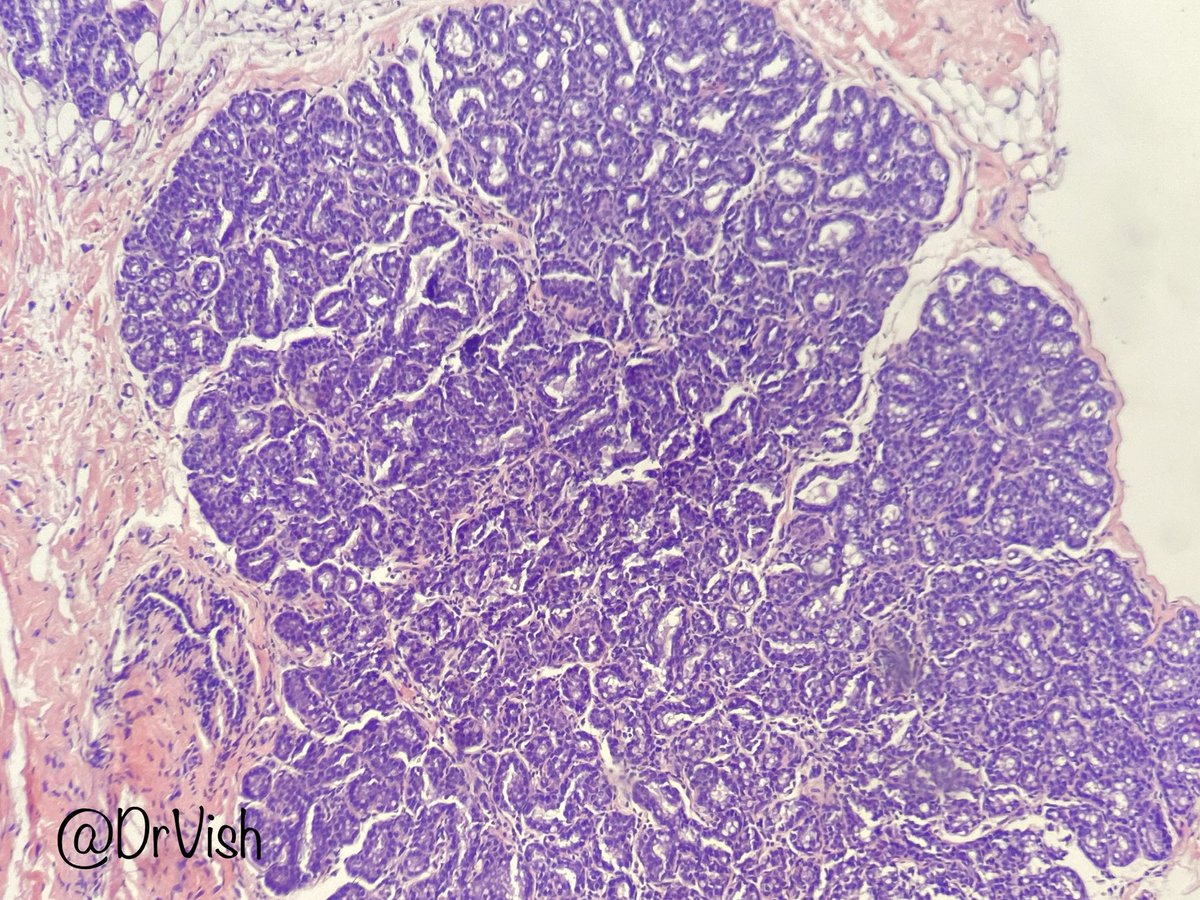

@DrVish

Vish Killari MD MPH

5 years

Differentials first nuclei with grooves. Please add to the list: solid pseudopapillary neoplasm #RandomPath @5_3shivani @DrAKumarPath @KMirza @Miryousufkhan3 @MitulModiMD @Gagandeepk5MD @ariella8 @EviAbadaMD @TheKarenPinto @kkuanMD @KusafukaK @padmapathology1 @debpratik

@Sujata_path

Sujata

Brunner tumor